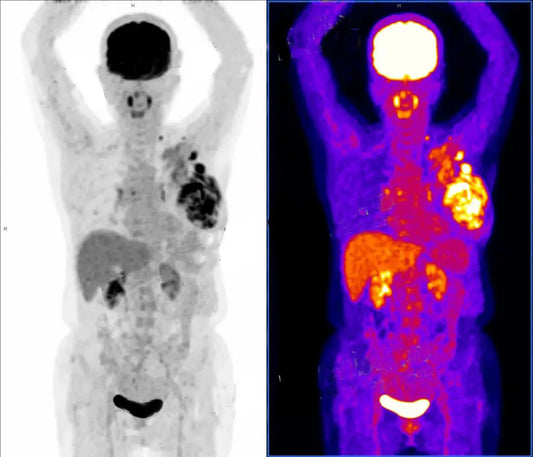

Diagnosis and Treatment of Rare Cardiac Conditi...

Mrs. Lim, a 58-year-old Malaysian patient, was initially misdiagnosed with idiopathic pulmonary arterial hypertension (IPAH). After a comprehensive diagnostic evaluation in Beijing, she was correctly diagnosed with a double-chambered right...